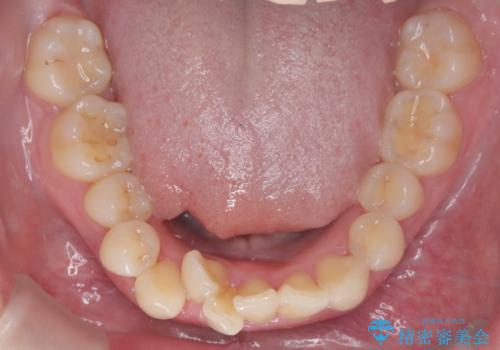

- 患者様は、下顎前歯のガタつきを改善したいとのことで来院されました。診察の結果、スペース不足により前歯が重なっている状態でした。抜歯をせずに並べると前歯が前方に突出してしまうため、下顎の前歯を1本抜歯し、インビザラインで矯正する治療計画を立てました。できる限り追加のアライナーを使用せずに治療を完了できるよう、初回の治療計画を慎重に設計しました。

下顎前歯を1本抜歯し、歯列のスペースを確保。その後、インビザラインを用いて計画通りに歯を移動させ、噛み合わせも整えました。患者様の協力もあり、ゴムかけなどを適切に行い、予定通り1年で治療を完了。追加アライナーを使用することなく、計画通りに治療を終えることができました。患者様からは「思ったより早く終わり、仕上がりにも満足している」と喜びの声をいただきました。